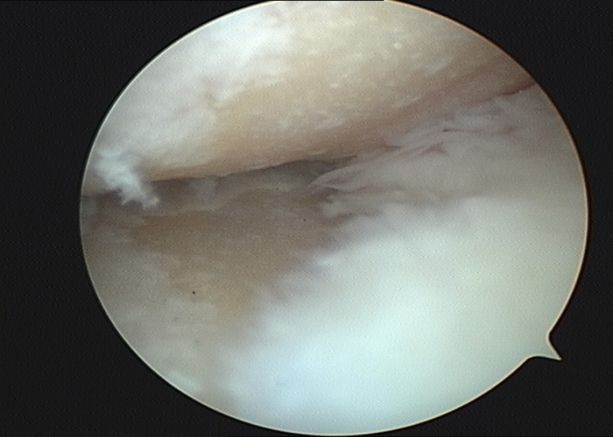

第三階梯:修復(fù)性治療。當(dāng)保守治療無(wú)法滿意控制病情時(shí),可考慮微創(chuàng)或矯形手術(shù)。①關(guān)節(jié)鏡清理術(shù):通過(guò)微創(chuàng)切口,清除關(guān)節(jié)內(nèi)的炎性滑膜、破碎的軟骨和游離體。②截骨術(shù):通過(guò)矯正下肢力線,將身體重量從磨損嚴(yán)重的一側(cè)轉(zhuǎn)移到相對(duì)健康的一側(cè)。